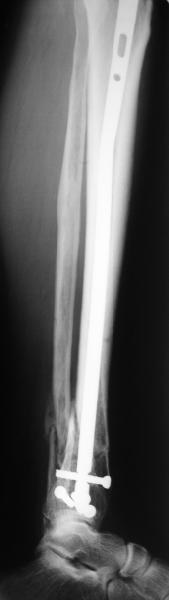

A typical case is attached, also an image with intra-op reduction obtained by a small wire distractor, in the moment of insertion a Poller wire in AP direction. Fixation by a SIGN nail. Despite the fibula was not fixed healing was obtained with the unchanged alignment.

I am just trying to illustrate that prevention of 1)tibial valgus and 2)loss of reduction can be provided without fibular plating. Small changes of conventional nailing techniques allow to maintain reduction of the tibia reliably without adjunctive fibular stabilization.

In delayed cases acute length restoration performed only in the tibia may leave the fibula shortened thus change the mortise. So it is reasonable to restore length of both bones simultaneously by distractor and fix the fibula not with open reduction and plating but just by a single perQ screw. Example attached.